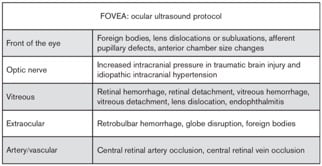

Figure 5. Suggested scanning protocol by Kilker et al 4